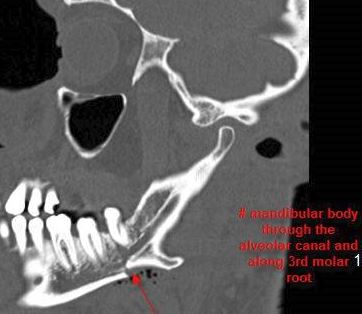

There is bony injury or displacement of the body, angle, ramus, parasymphyseal region, alveolar ridge, and condylar and coronoid process of the mandible. [In case of fracture, describe complexity and displacement]. [Yes/No]

There are dental fractures and/or missing or displaced teeth. [Yes/No]